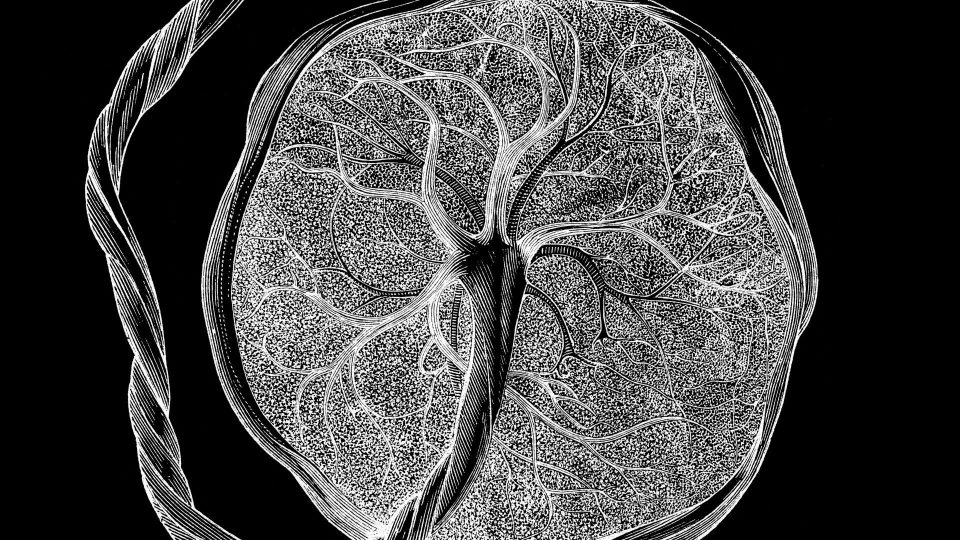

Scientists have unveiled a detailed “atlas” of the placenta and uterus, showing how these unique tissues grow and evolve throughout pregnancy to accommodate a developing fetus.

In total, the team analyzed about 1.2 million placental and uterine cells, including 200,000 isolated cells and 1 million cells embedded in their original locations within the tissue.

For instance, early in pregnancy, certain fetal cells invade the uterus and its major arteries, helping to establish blood flow to the placenta. Using machine learning, the researchers predicted how deeply a given cell would invade the uterus based on its gene activity. When this invasion goes awry — for example, if cells do not penetrate deeply enough or they penetrate too deeply — it can contribute to complications like preeclampsia or placenta accreta.